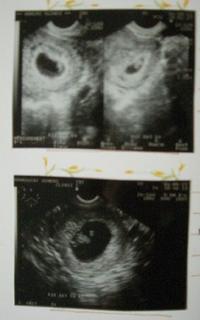

小さな赤ちゃんのいる部屋を確認。

不思議でとても嬉しい瞬間。

妊娠発覚後の2週間後に赤ちゃんの心臓を確認。

たった2週間で赤ちゃんが確実に成長している。

(チャ~の7週、8週目の超音波写真)